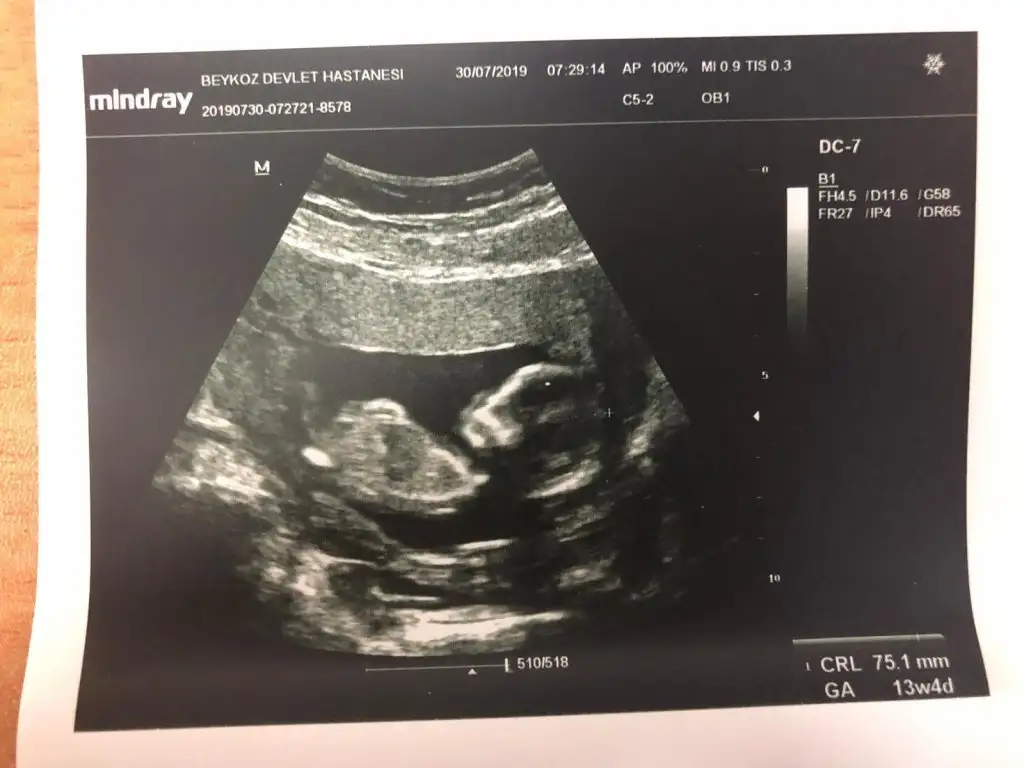

Bu usg ye gore kiz canim nubu zorda olsa gorunuyor paralel gonlundeki olsun ben sadece bu usg ye gore yorum yapiyorum dr daha detayli goruyorBebek göstermedi bacak arasını doktor da göremedim kemik yapısından kıza benzetiyorum görmeden yüzde yüZ diyemem dedi![]()

Bacakları kapalı uyuyordu uyandiramadi doktor söyleyemedi 16 haftadayimNub için 11 yada 12 hafta olmalı minnoş baya buyuk sanırım dr sölemedimi 21 hafta takviminiz kız diyorum görüntüsüne![]()